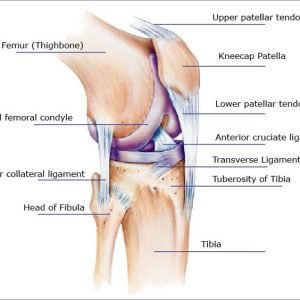

Understanding the Anatomy of the Outer Knee

To comprehend the possible causes of outer knee pain, it is essential to first understand the intricate anatomy of the knee joint. The knee is one of the body’s largest and most complex joints, composed of the femur (thigh bone), tibia (shin bone), patella (kneecap), and a network of ligaments, tendons, and cartilage. The outer knee, in particular, is home to several structures that can become sources of discomfort.

The iliotibial band is a thick band of fibrous tissue that runs along the outside of the thigh, from the hip to just below the knee. The ITB plays a crucial role in stabilizing the knee joint during movements. Overuse, friction, or inflammation of the ITB can lead to iliotibial band syndrome, a common cause of outer knee pain.

The lateral collateral ligament is one of the four major ligaments in the knee, providing stability to the joint by connecting the femur to the fibula. Injuries or damage to the LCL can result in lateral collateral ligament pathology, leading to pain and instability on the outer side of the knee.

The lateral meniscus is a C-shaped cartilage structure that acts as a cushion between the femur and tibia. Tears or degeneration of the lateral meniscus can cause pain, swelling, and discomfort, particularly on the outer aspect of the knee.